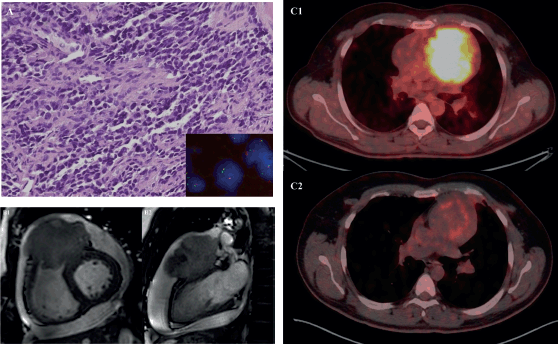

Figure 3. 31-year-old male with desmoplastic small round cell tumour arising from right ventricular outflow tract – (a): Histological photomicrograph showing a malignant round cell tumour with undifferentiated tumour cells with high NC ratio and scanty cytoplasm. (H&E 200×); FISH performed using fusion probes for Ewsr1-WT1 gene showing fused signals indicating EWSR1-WT1 fusion (Inset); (b): Cardiac MRI – short axis view (B1) and 2 chamber view (B2) showing expansile proliferative mass lesion involving the right ventricular outflow tract; (c): FDG PET-CT before (C1) and after (C2) 6 cycles of VAC chemotherapy.

Figure 4. PET scans of a patient with locally advanced/unresectable cardiac angiosarcoma (a): Before chemotherapy and (b): After 5 cycles of single-agent gemcitabine.